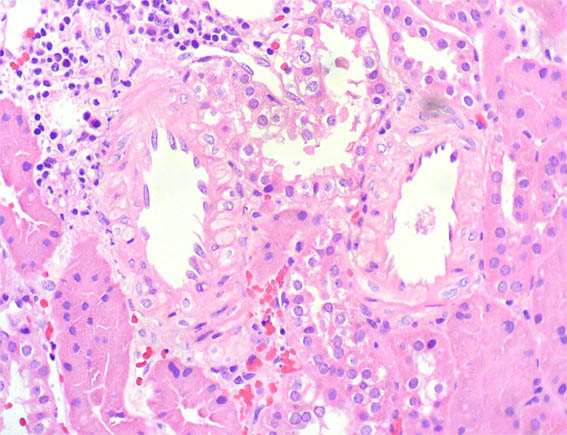

An allograft kidney biopsy was done. See the images.

Figure 3. H&E, X400.